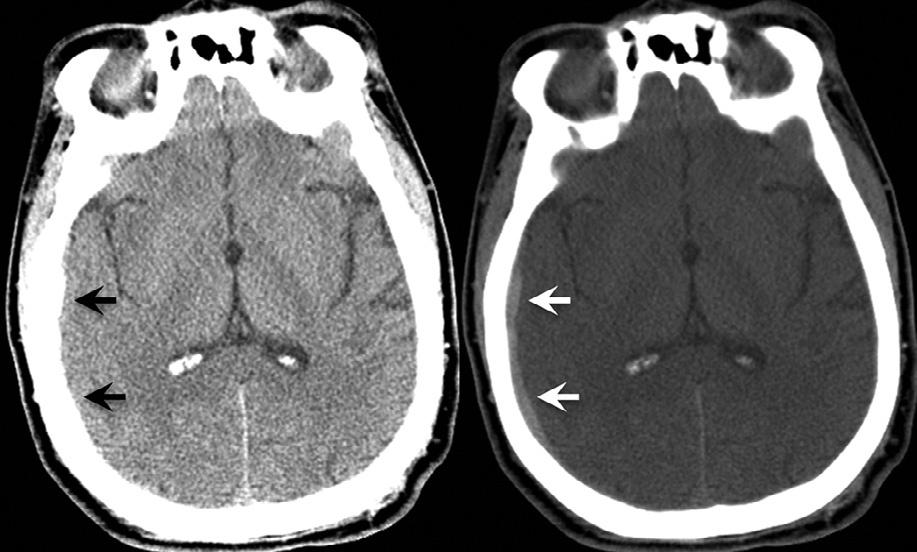

suchsettings,asubtlecrescenticsubduralhematoma ( 90HU)wouldappearequallyasbrightastheadjacent skull( 1000HU),andhencebeundetectable.Conversely,fat( –30HU)andair( –1000HU)would appearequallydark,andhence,airwithinintraorbital fatresultingfromaparanasalsinusfracturewouldalso beundetectable(Fig.1.3).Byexpandingthewindow widthdisplayandcenteringthegrayscaleatahigher HUlevel,thedifferenceindensitybetweenthesame subduralhematomaandadjacentbonecanbemade visuallyapparent.Similarly,ithasbeensuggestedthat subtlevasogenicedemainacutestrokecanbemoresensitivelydetectedbysoftcopyimagereviewusingnarrowedwindowwidthdisplaysettingsthatexaggerate theHUdifferencesbetweengrayandwhitematter (Levetal.,1999).

Fig.1.3. Computedtomographyimageatlefthascenter-level displaysettingof30HUandwindowwidthof100HU.The imageatrighthascenter-level80HUandwindowwidth 200HU.Withthedisplaysettingsontheright,thesubtlecrescenticsubduralhematomaadjacenttobonebecomesvisually apparent.